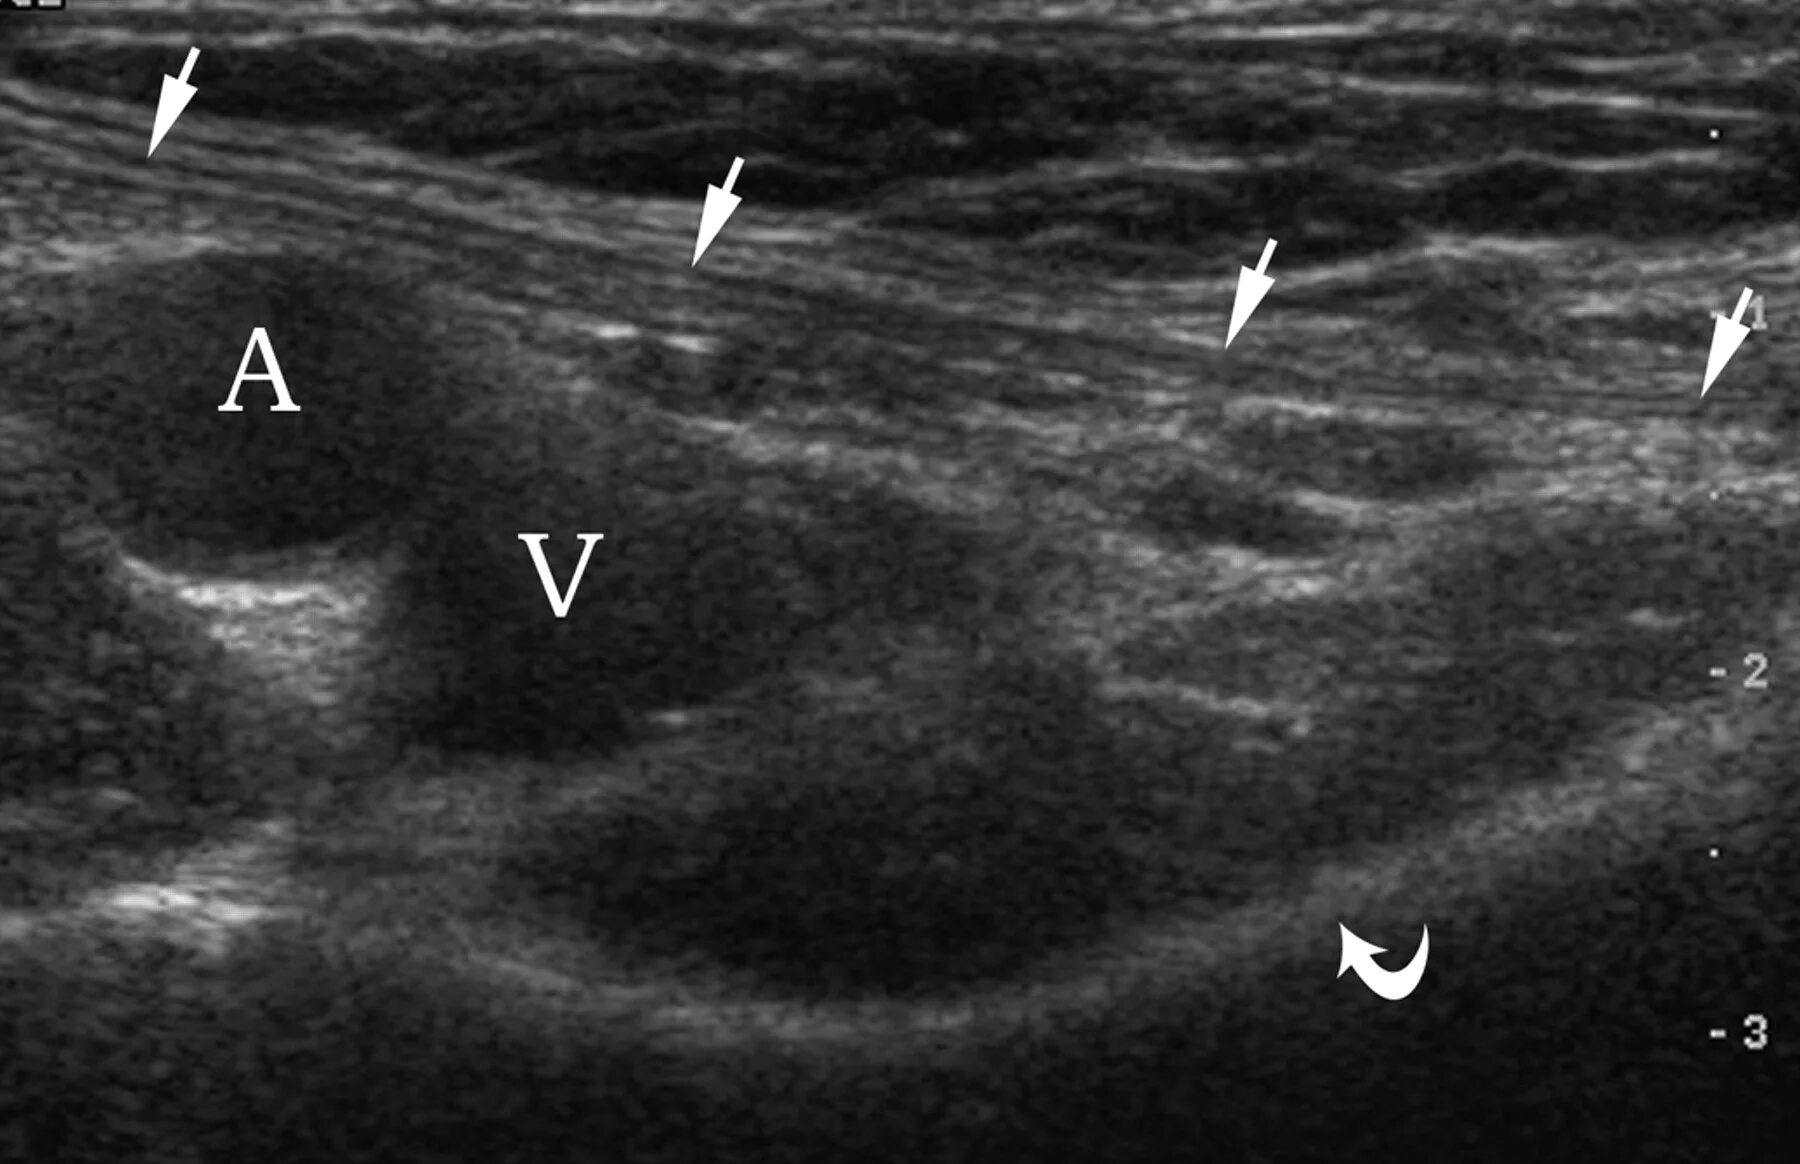

Паховая грыжа код мкб 10 у взрослых